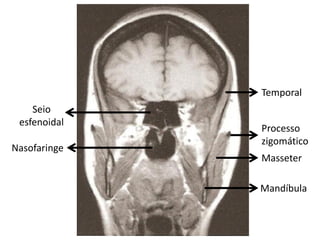

Tomografia Computadorizada do Crânio

• Alto grau de confiabilidade;

• Qualquer suspeita patológica envolvendo o encéfalo é indicativo de

TC;

Alterações visualizadas:

   Neoplasias;

   Lesões;

   Tumores

   Metástases;

   Hemorragia intracraniana;

   Aneurisma;

   Abscesso;

   Atrofia cerebral;

   Alterações pós-traumáticas;

   Alterações congênitas.

Temporal

Seio

esfenoidal

Processo

zigomático

Nasofaringe

Masseter

Mandíbula